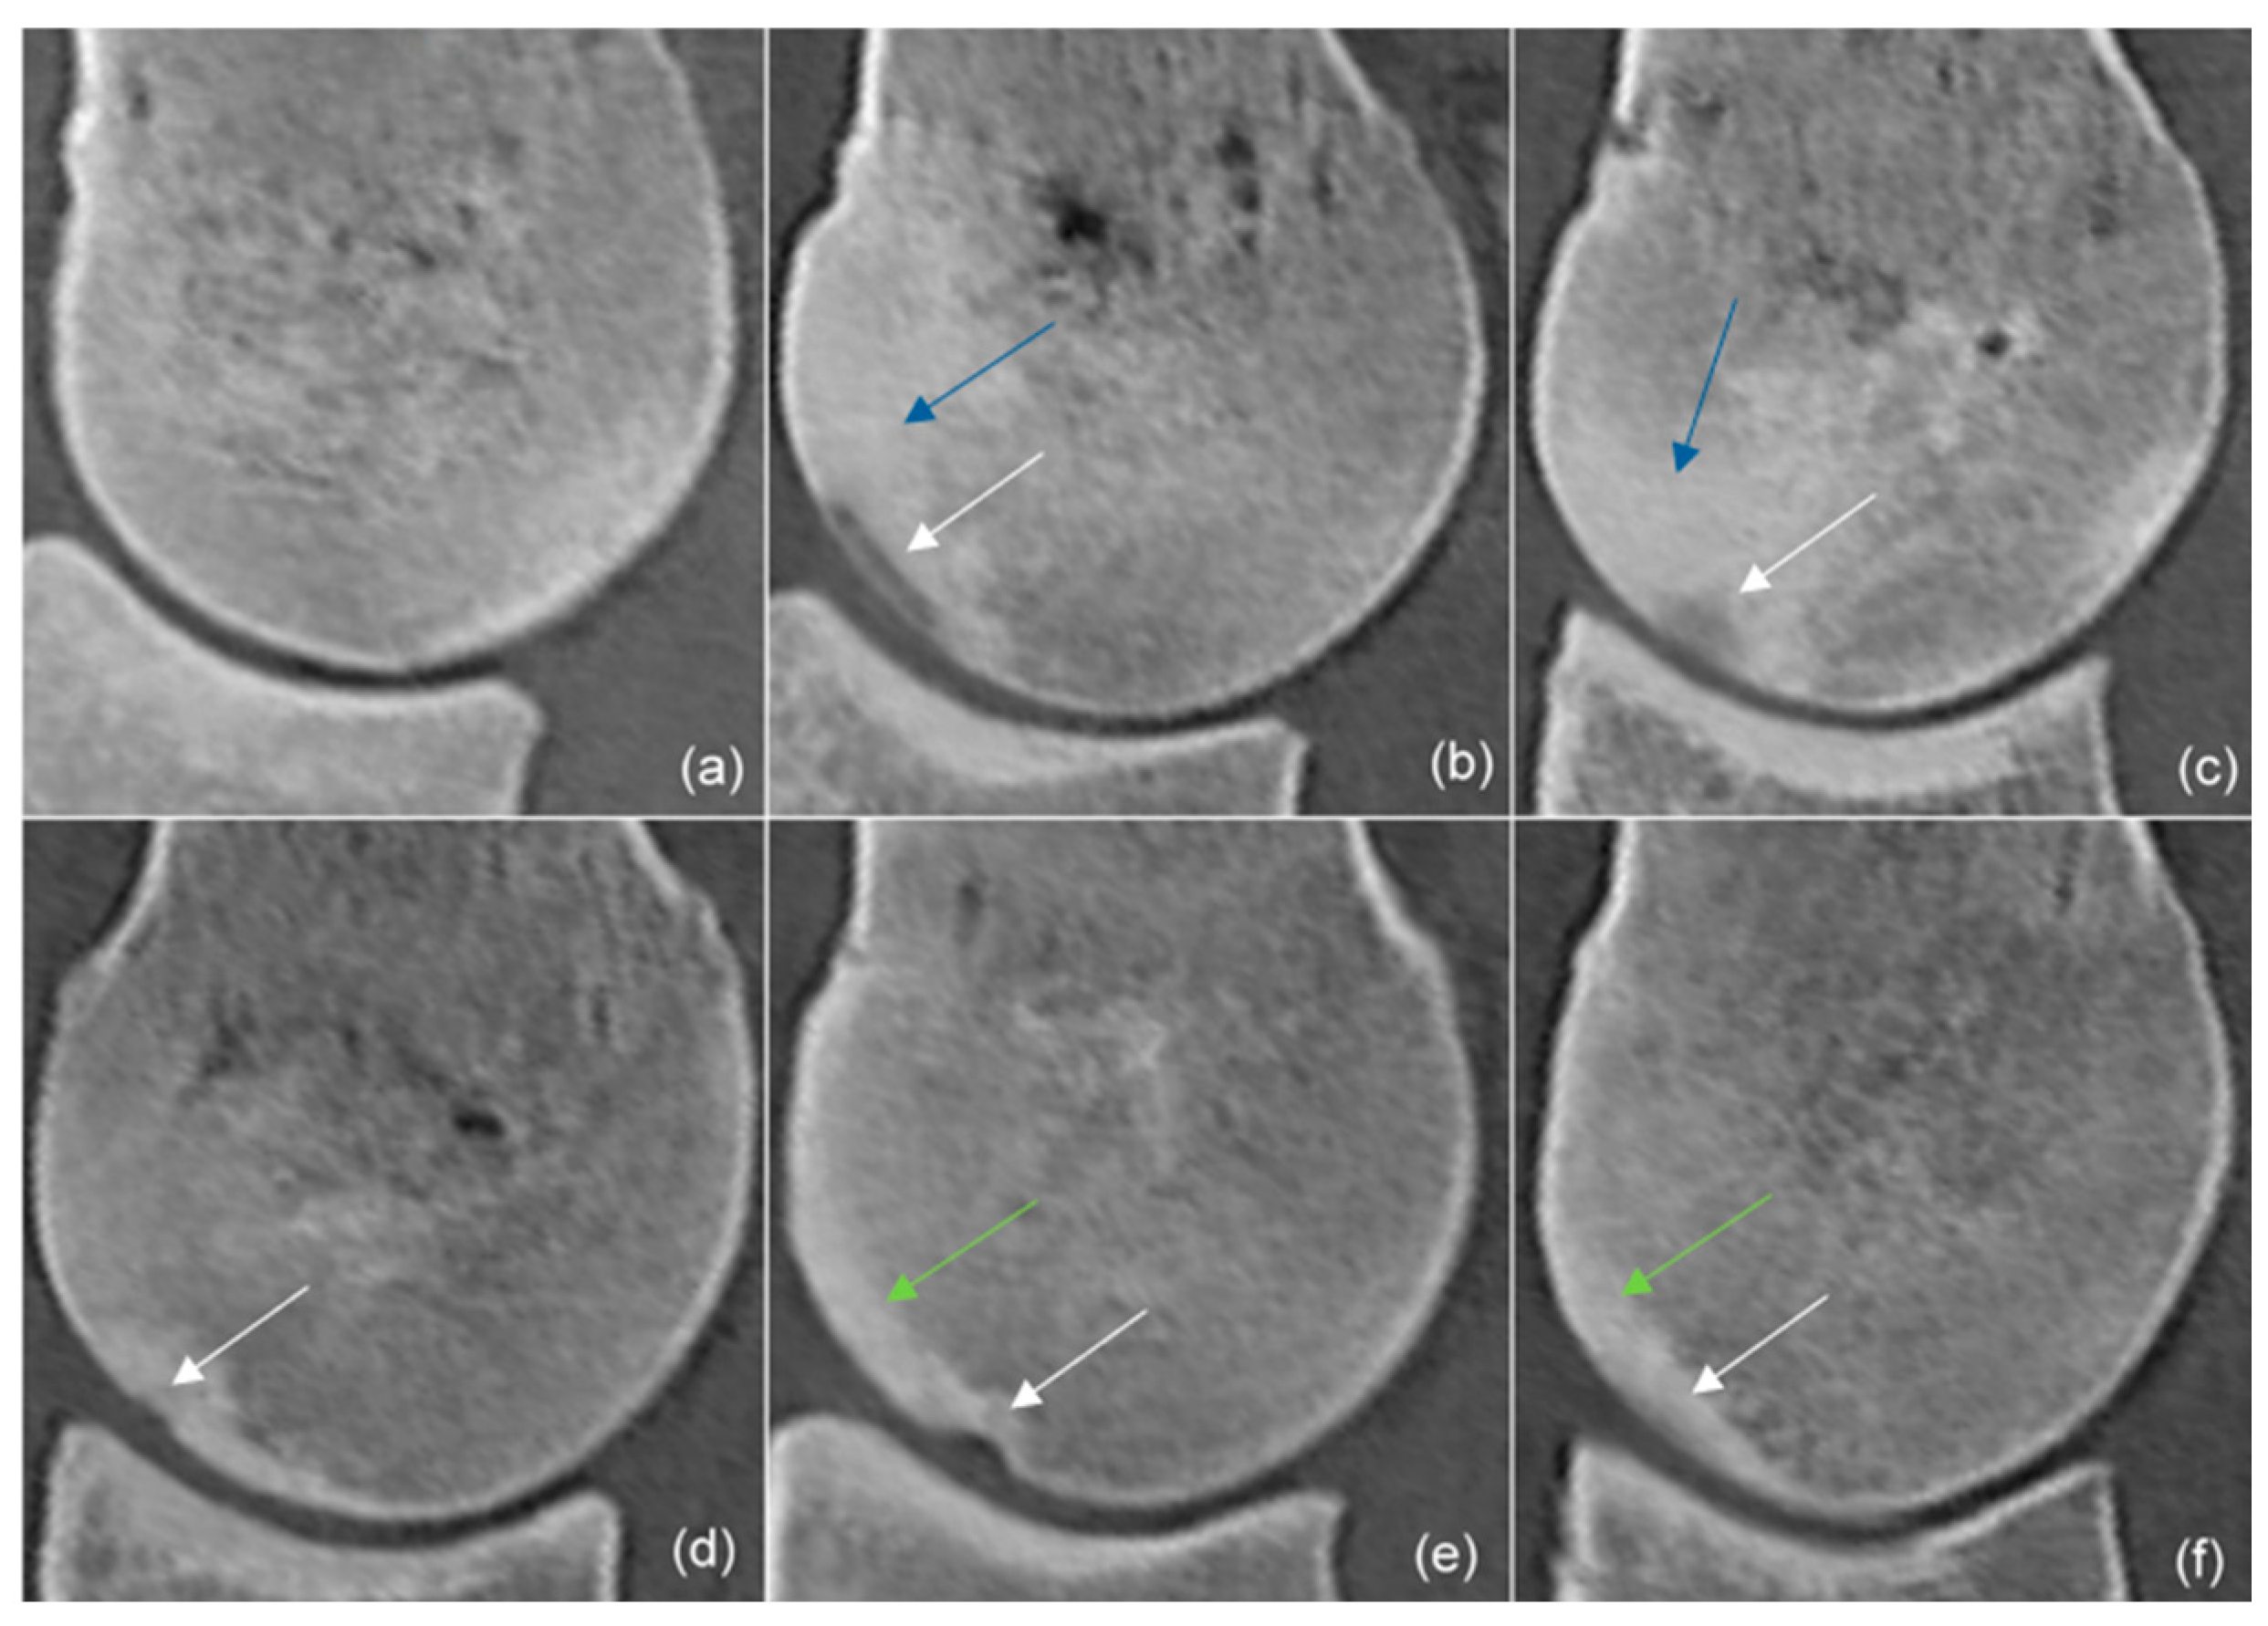

| Shape | ||||

| Proximodistally elongated | 12 | 6 | 5 | |

| Extending towards trabecular bone | 16 | 10 | 5 | |

| Depression | 1 | 1 | 1 | |

| Indentation | 2 | 1 | 1 | |

| Subtle | 2 | 4 | 2 | |